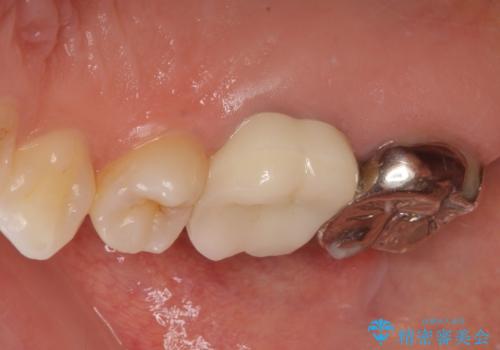

拡大鏡視野下で虫歯の除去を行い、オールセラミッククラウンに適した形に整えました。

型どりはシリコーン印象材にて精密印象をしています。

適合もよく、機能的に問題もなく、見た目も満足されていました。